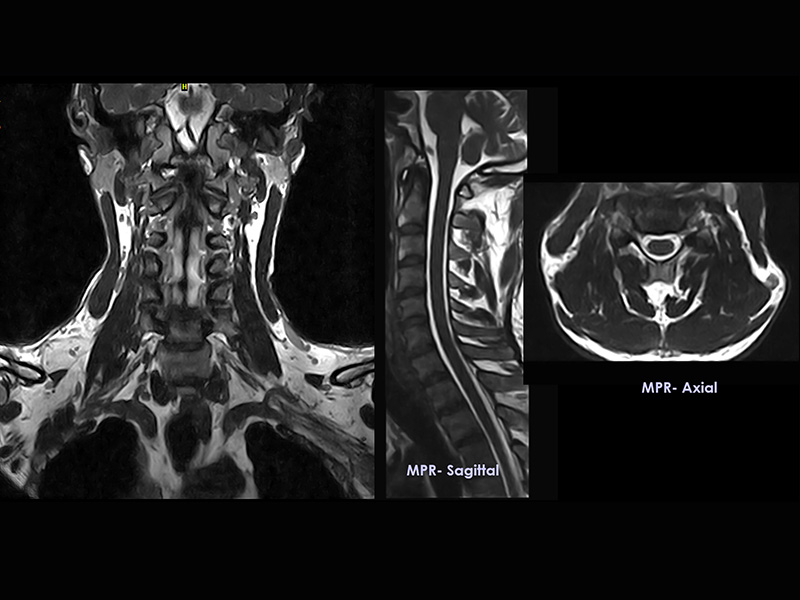

Klinické snímky